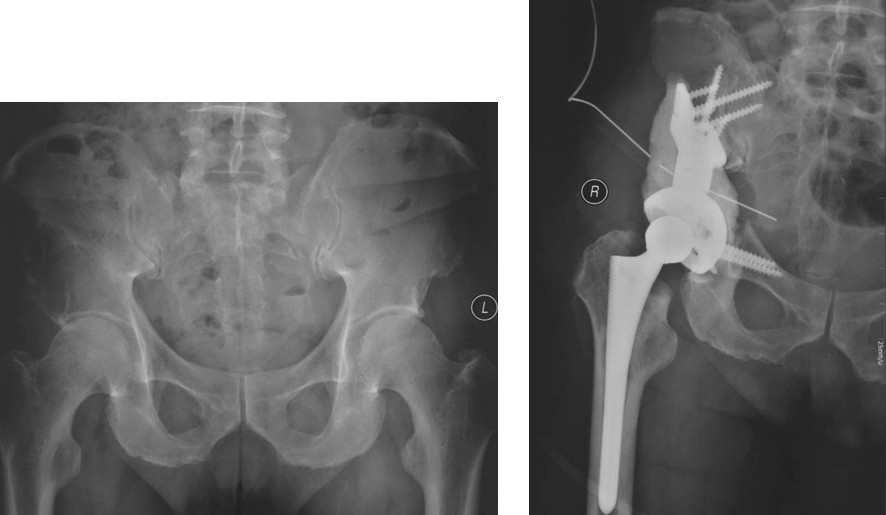

本组病例中不同部位髋臼转移癌的手术方式(图1):I型:髋臼下壁骨破坏、上壁及内、外侧壁完整, 采用肿瘤刮除、普通水泥型全髋置换术。II型:髋臼内、外侧壁破坏,上壁骨质完整, 采用带翼网杯+水泥型全髋置换术。 III型:髋臼上壁及内、外侧壁均破坏,采用肿瘤刮除后、骨水泥填充髋臼上壁骨缺损,带翼网杯+水泥型全髋或组合式人工半骨盆。IV型:孤立性骨盆转移, 以治愈为目的, 采用肿瘤整块切除,组合式人工半盆置换术。

Ⅲ型:髋臼内壁、顶部及外侧壁均破坏。仅使用带翼网杯的全髋假体是不够的。在这种情况下,需要在骨盆缺损处放置数根斯氏针以便于将位于解剖位置的髋臼假体所承受的应力传导至脊柱(1-3)。在大多数髋臼周围破坏广泛的病例,需要采用扩大的髂股骨切口入路,以便于探查骨盆内外侧区域。在显露清楚后,自髋臼缺损处沿残留的正常髂骨向骶髂关节方向钻入2-3根斯氏针,并越过关节达到骶骨。应采用较粗的斯氏针,术中还需要X线监测以保证斯氏针的位置。在钻入斯氏针的同时,应用手指触摸坐骨切迹,以保证斯氏针的方向,防止其穿入骨盆内壁。当髋臼缺损较大时,还可以自前部髂嵴向前柱的耻骨及后柱的坐骨钻入更多的斯氏针做进一步的加强。在髋臼假体顶部切断斯氏针,并安装带翼网杯,在髋臼深部可以用金属钛网加强骨水泥固定。术后病人可全部负重行走,但需置患肢外展中立位约4周时间以防止脱位。也有采用马鞍式假体置换的报道, Benevenia等对20例髋臼III型转移瘤患者进行了马鞍假体置换,术后MSTS 93评分平均16.6分,多数病人可以扶拐行走(5)。对于髋臼上壁及内、外侧壁均破坏的HarringtonIII型患者,本组病例中,有7例患者采用了肿瘤刮除后、于骶髂关节处植入3-4枚斯氏针, 骨水泥填充髋臼上壁骨缺损,水泥型全髋重建髋关节。其中,有2例患者出现下地后髋部痛疼,负重时髋部不稳定。考虑为负重时骶骨内斯氏针承受较大剪力, 出现髋关节不稳。因此,在本组病例中,我们对4例Ⅲ型患者实施了整块切除、可调式人工半骨盆置换术。术后6周患者可以扶拐下地行走。平均MSTS93评分为23.3分。

图4,女,52岁,乳腺癌髋臼转移, Harrington III型

图5,男,69岁,肾癌髋臼转移, Harrington IV型